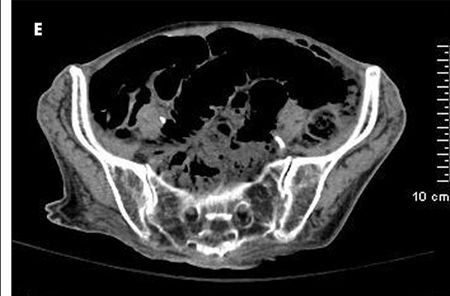

The patient complained of diffuse abdominal pain. She had an erythematous swelling around the right iliac fossa, abdominal guarding, and palpable crepitations. CT scan of the abdomen without contrast showed extensive portal venous air from the small branches in the periphery to the main portal and splenic veins (A and B). Considerable gaseous distention of the small bowel (C and D) and dilated loops of the small bowel were also seen (D and E). These findings were consistent with pneumatosis intestinalis.